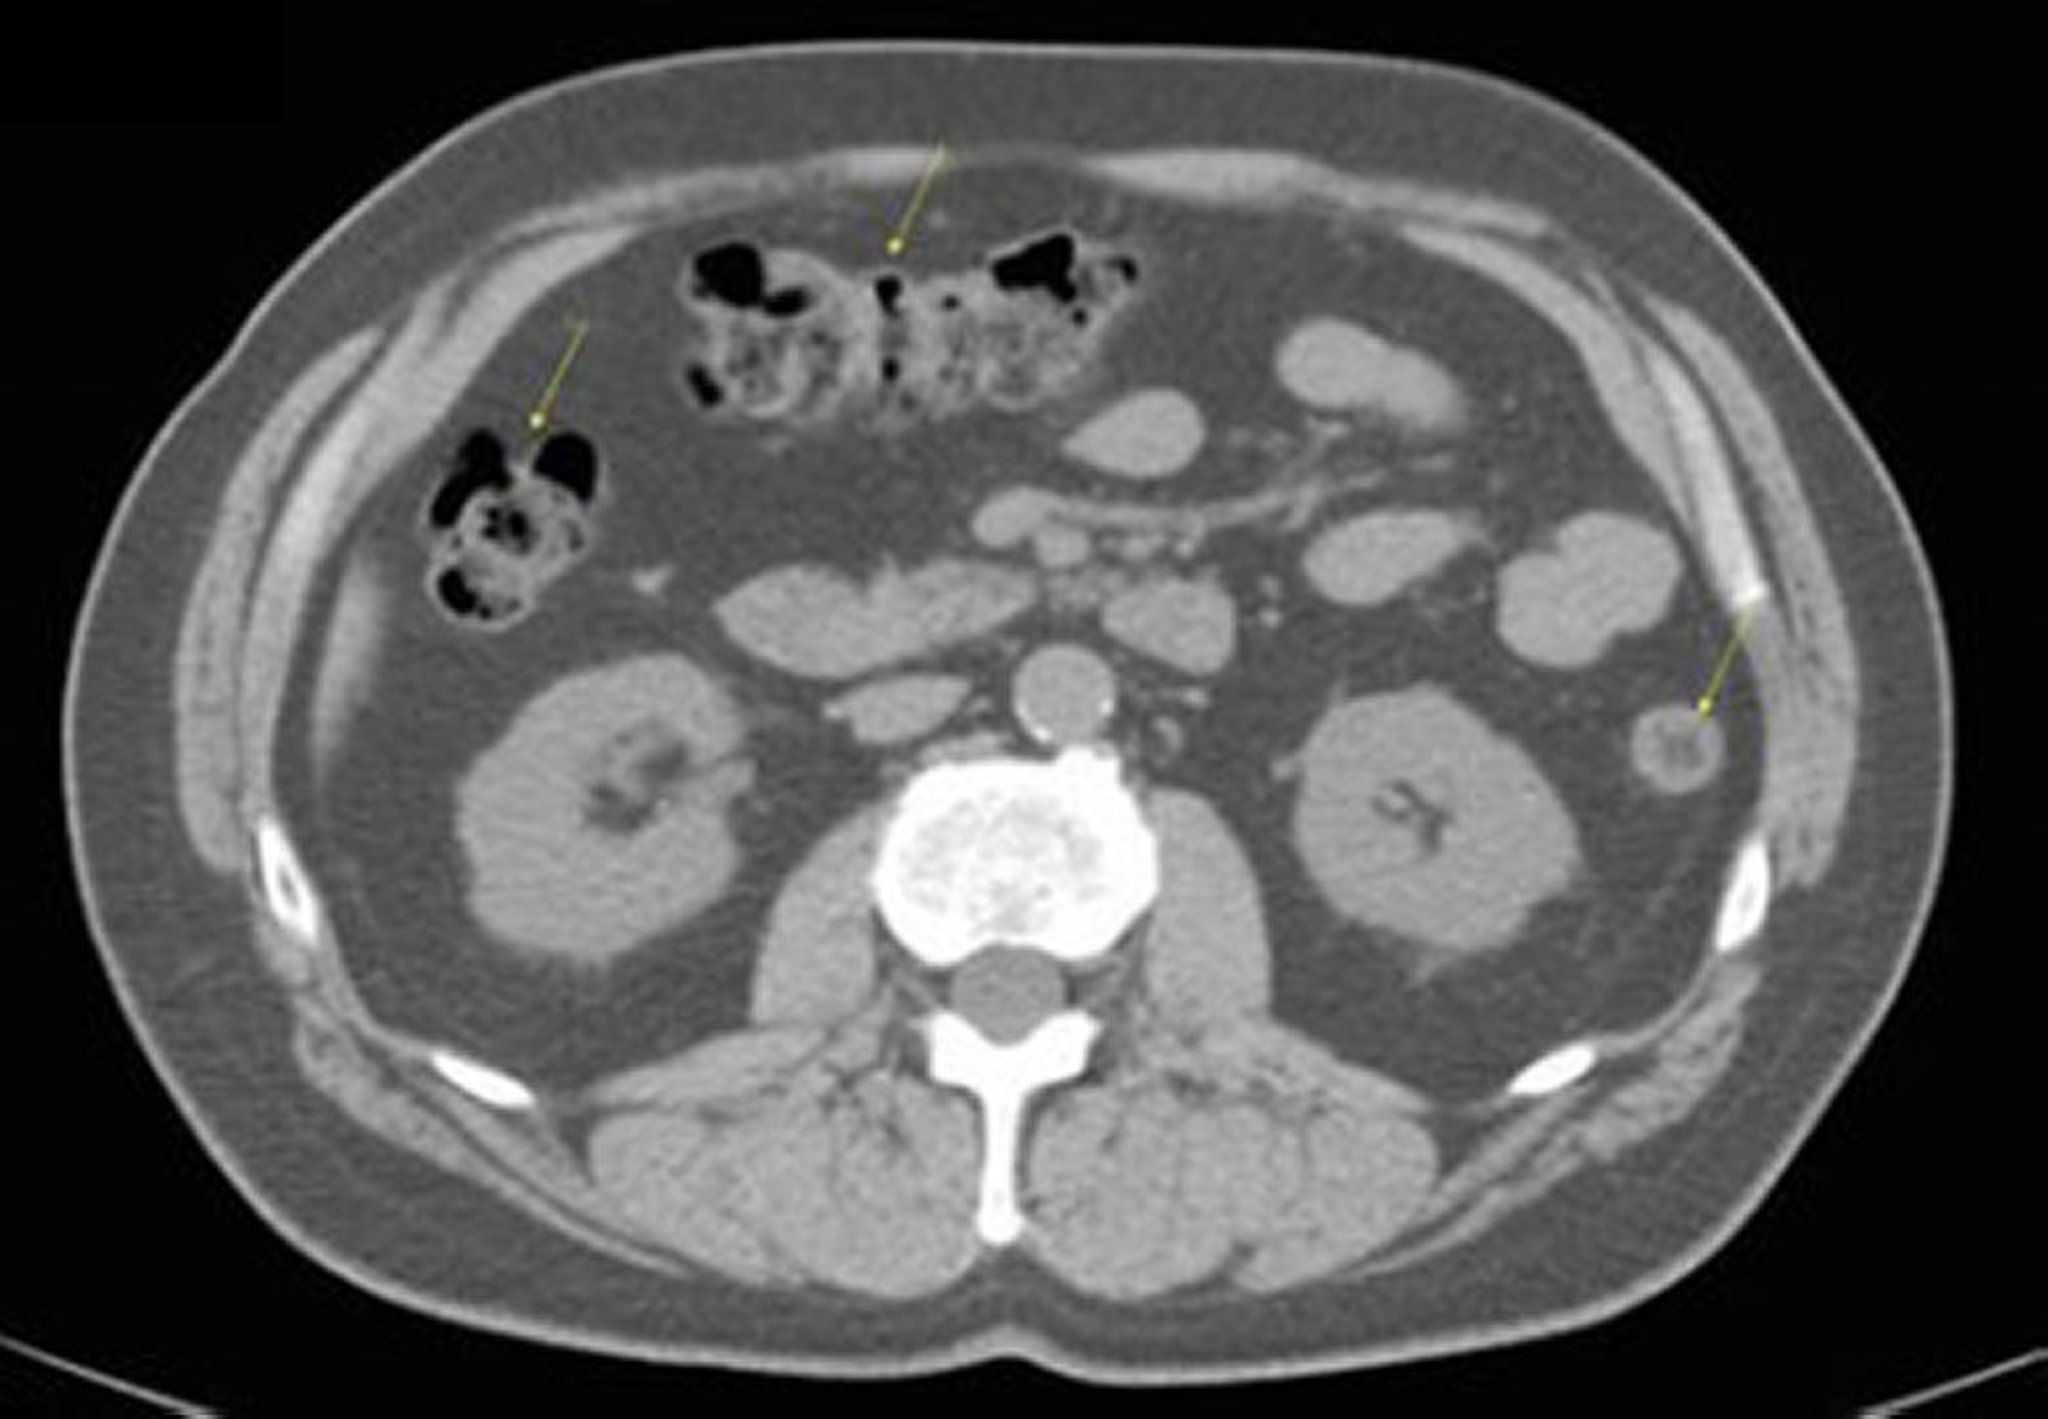

Noncontrast CT Scan of the Abdomen and Pelvis Showing Normal Anatomy (Slide 17)

This image shows the colon (arrows).